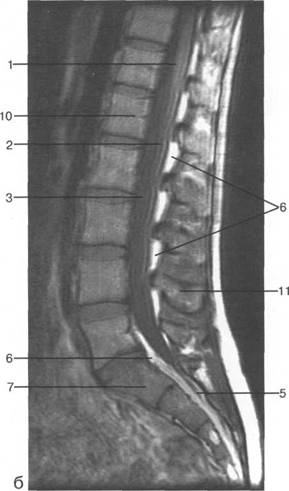

conus medullaris) LIU.

ThXI1;

ThK-Thx.

Thlx; Thlx;